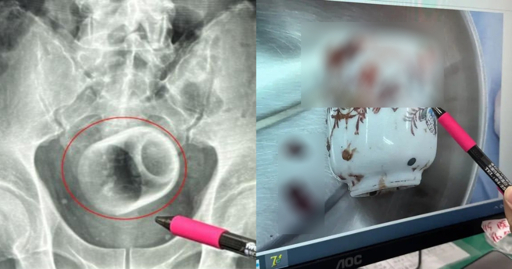

schizoidman@lemmy.zip to Not The Onion@lemmy.worldEnglish · 26 天前Man in Taiwan somehow gets 8cm by 6cm ceramic cup in bottom, claims it got there 'by accident'mothership.sgexternal-linkmessage-square50linkfedilinkarrow-up1227arrow-down18

arrow-up1219arrow-down1external-linkMan in Taiwan somehow gets 8cm by 6cm ceramic cup in bottom, claims it got there 'by accident'mothership.sgschizoidman@lemmy.zip to Not The Onion@lemmy.worldEnglish · 26 天前message-square50linkfedilink